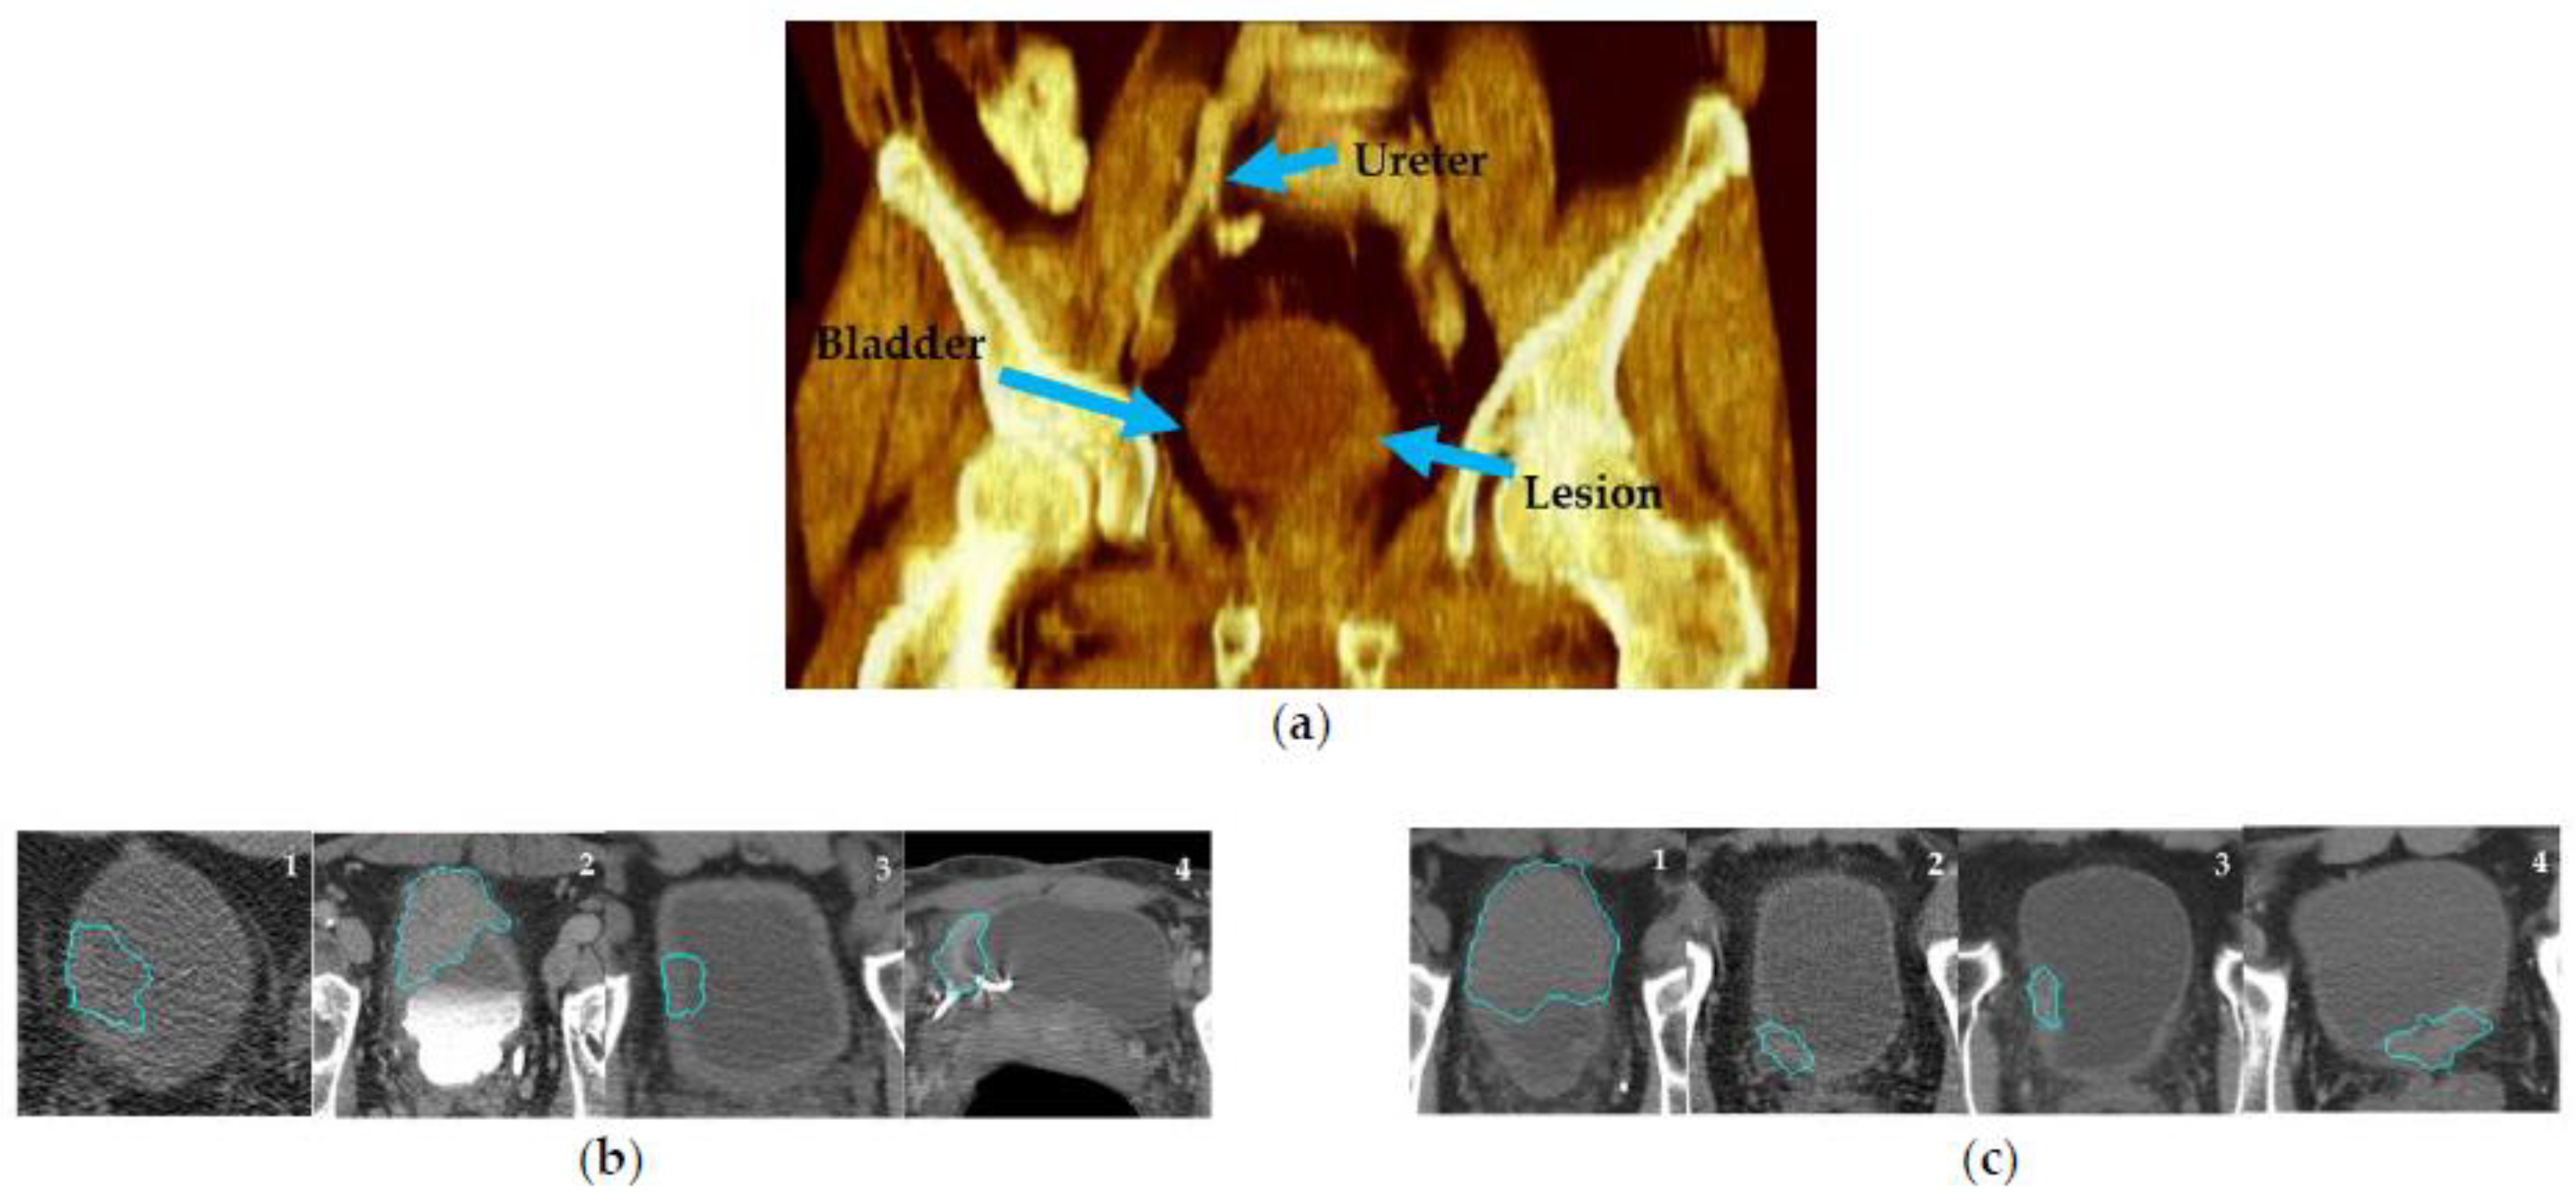

2.3. CTU Scans Processing

2.4. Radiomics Model

2.5. Deep-Learning Model

- Hadjiiski, L.; Chan, H.-P.; Caoili, E.M.; Cohan, R.H.; Wei, J.; Zhou, C. Auto-initialized cascaded level set (AI-CALS) segmentation of bladder lesions on multidetector row CT urography. Acad. Radiol. 2013, 20, 148–155. [Google Scholar] [CrossRef]

- Sun, D.; Hadjiiski, L.; Alva, A.; Zakharia, Y.; Joshi, M.; Chan, H.-P.; Garje, R.; Pomerantz, L.; Elhag, D.; Cohan, R.H. Computerized decision support for bladder cancer treatment response assessment in CT urography: Effect on diagnostic accuracy in multi-institution multi-specialty study. Tomography 2022, 8, 644–656. [Google Scholar] [CrossRef]

- Cha, K.H.; Hadjiiski, L.; Chan, H.-P.; Weizer, A.Z.; Alva, A.; Cohan, R.H.; Caoili, E.M.; Paramagul, C.; Samala, R.K. Bladder cancer treatment response assessment in CT using radiomics with deep-learning. Sci. Rep. 2017, 7, 8738. [Google Scholar] [CrossRef] [PubMed]

- Wu, E.; Hadjiiski, L.M.; Samala, R.K.; Chan, H.-P.; Cha, K.H.; Richter, C.; Cohan, R.H.; Caoili, E.M.; Paramagul, C.; Alva, A. Deep learning approach for assessment of bladder cancer treatment response. Tomography 2019, 5, 201–208. [Google Scholar] [CrossRef]